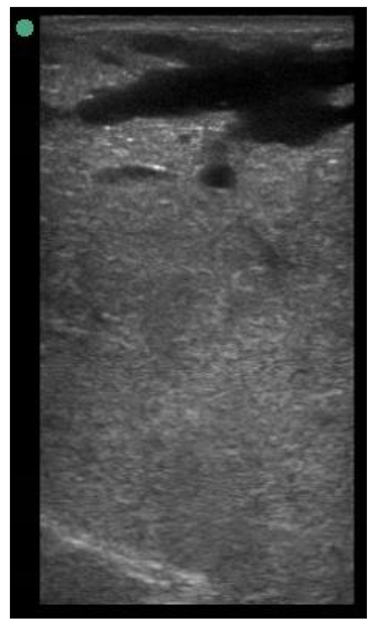

Appendix A. Drawing Templates of Mammary Ultrasound Images in Late Pregnancy, Early Lactation and Weaning in Yearling Ewes

Drawing template of mammary ultrasound images in late pregnancy (107 days of pregnancy; P107) in four different yearling ewes.

Drawing template of mammary ultrasound images in early lactation (29 days of lactation; L29) in four different yearling ewes.